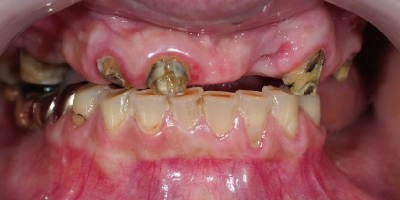

Case Study: All-on-4 Restoration

- Procedure: All-on-4 Full Mouth Restoration

- Patient: Suzan T. (from Canada)

- Problem: Unstable Upper denture.

- Time: 6 Days (Trip 1) Time: 7Days (Trip 2)